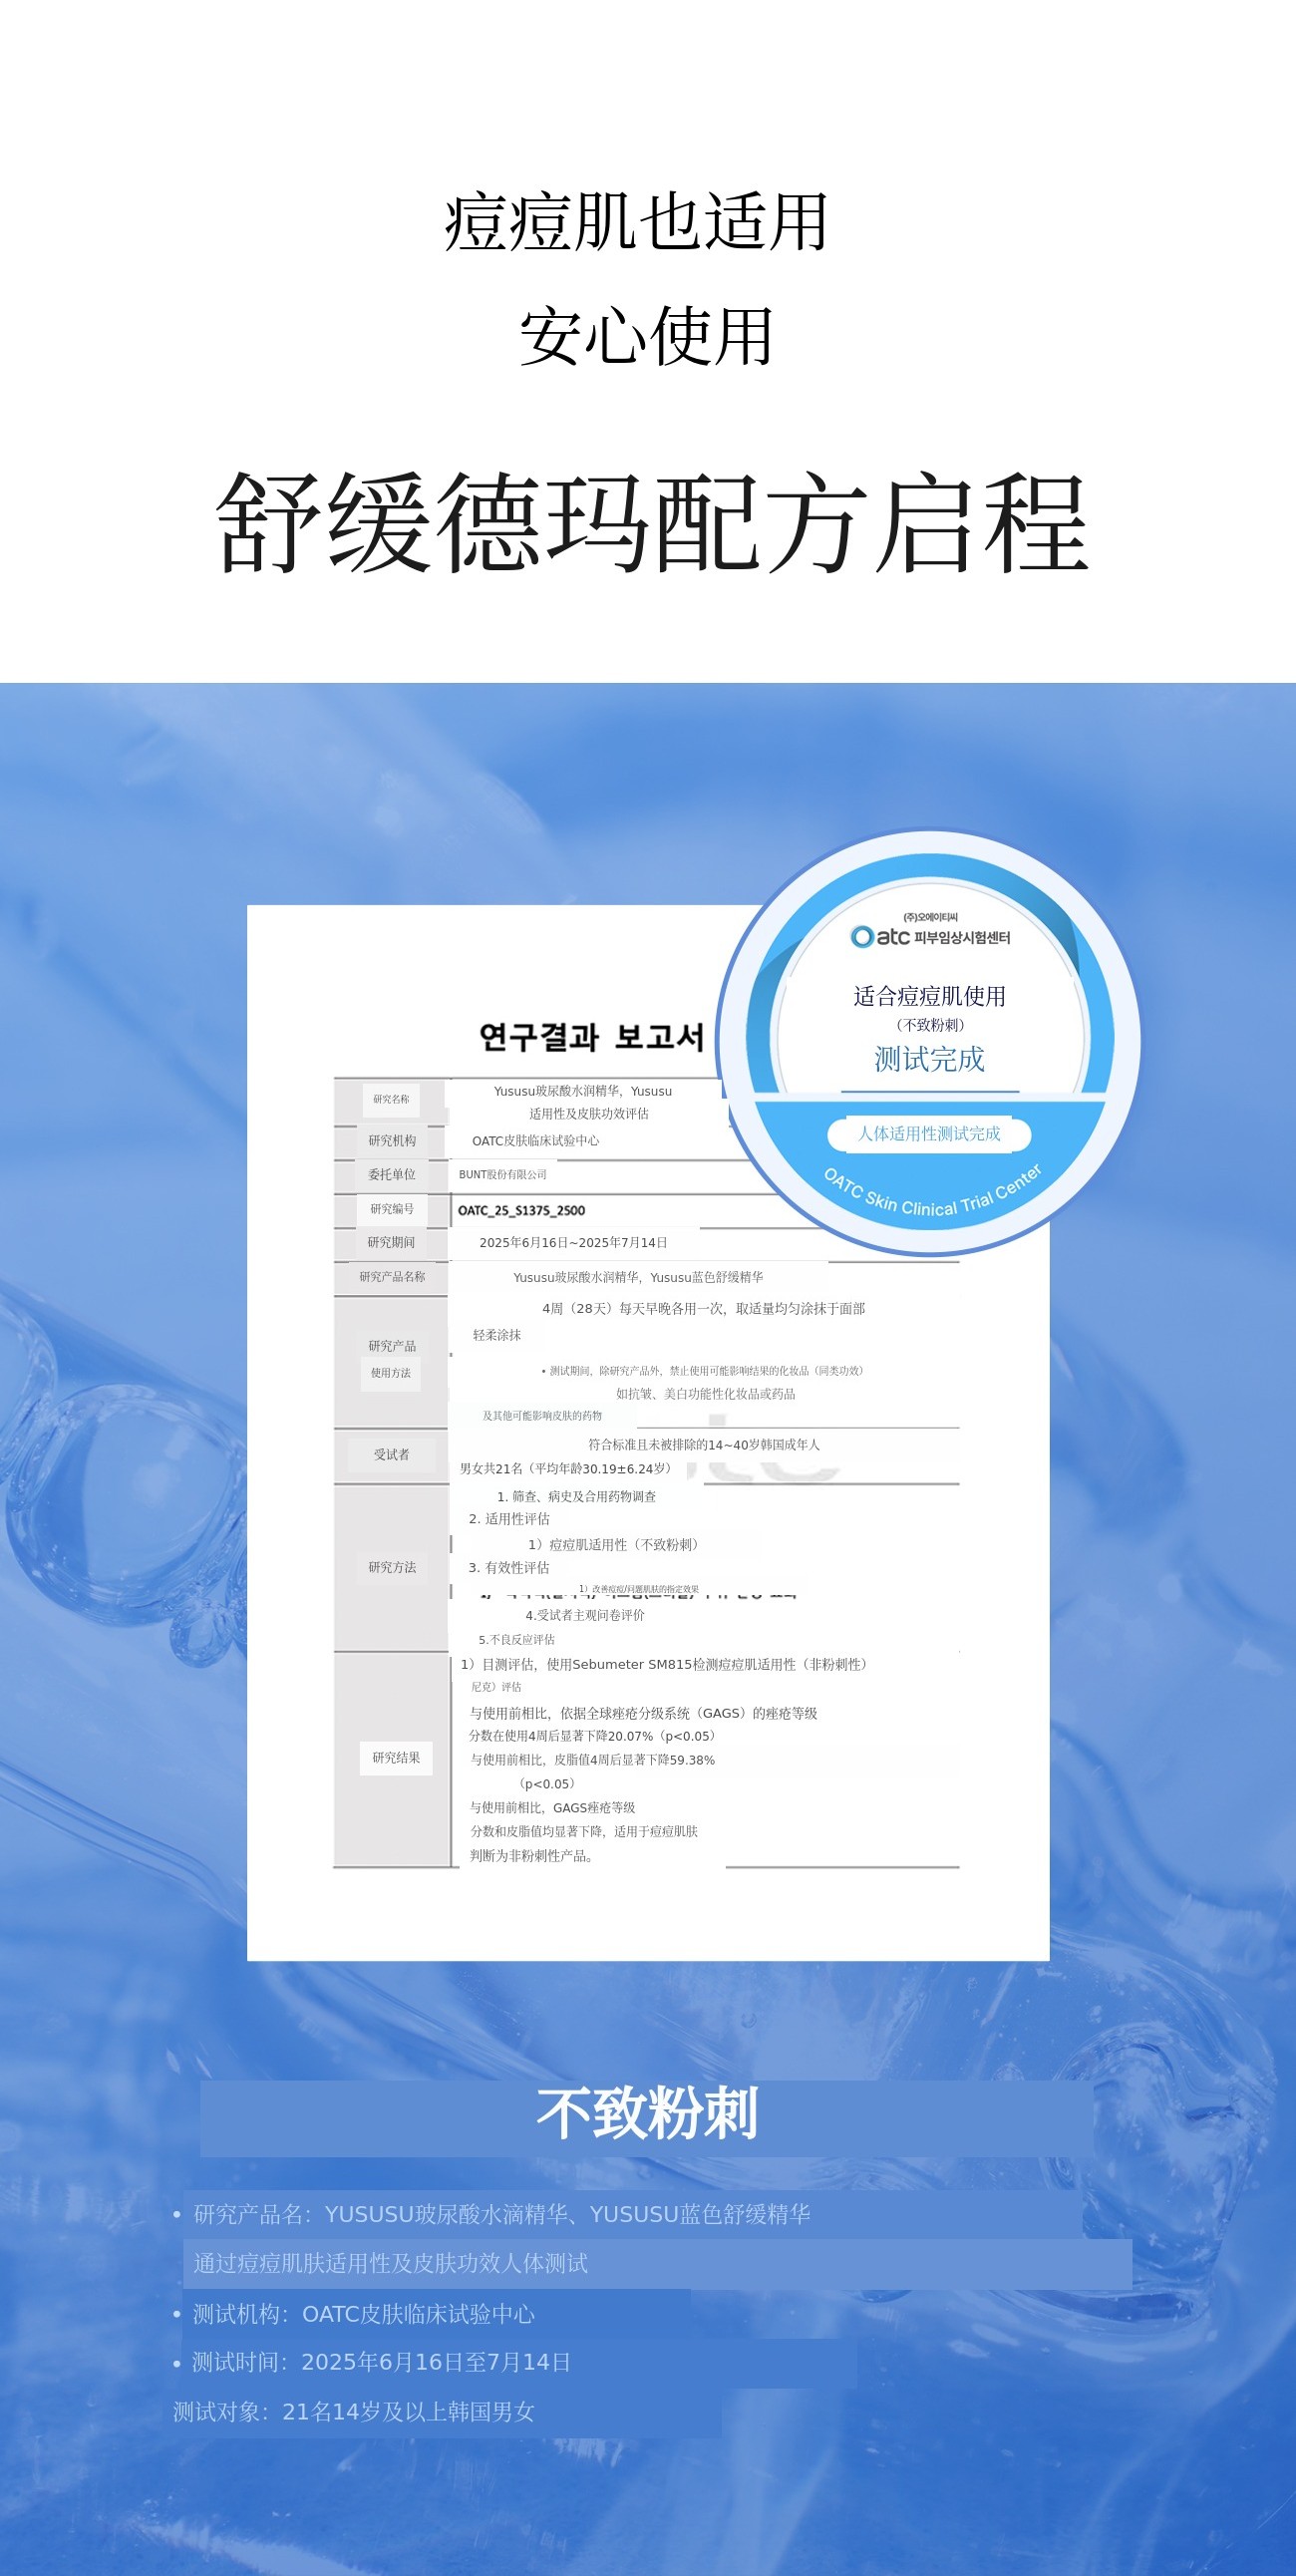

Q3. 痘痘肌、敏感肌也可以使用吗?

A. 可以!Yususu已完成无致痘性测试及敏感肌肤低刺激测试。 不含致痘成分,专为镇静设计,可安心使用。